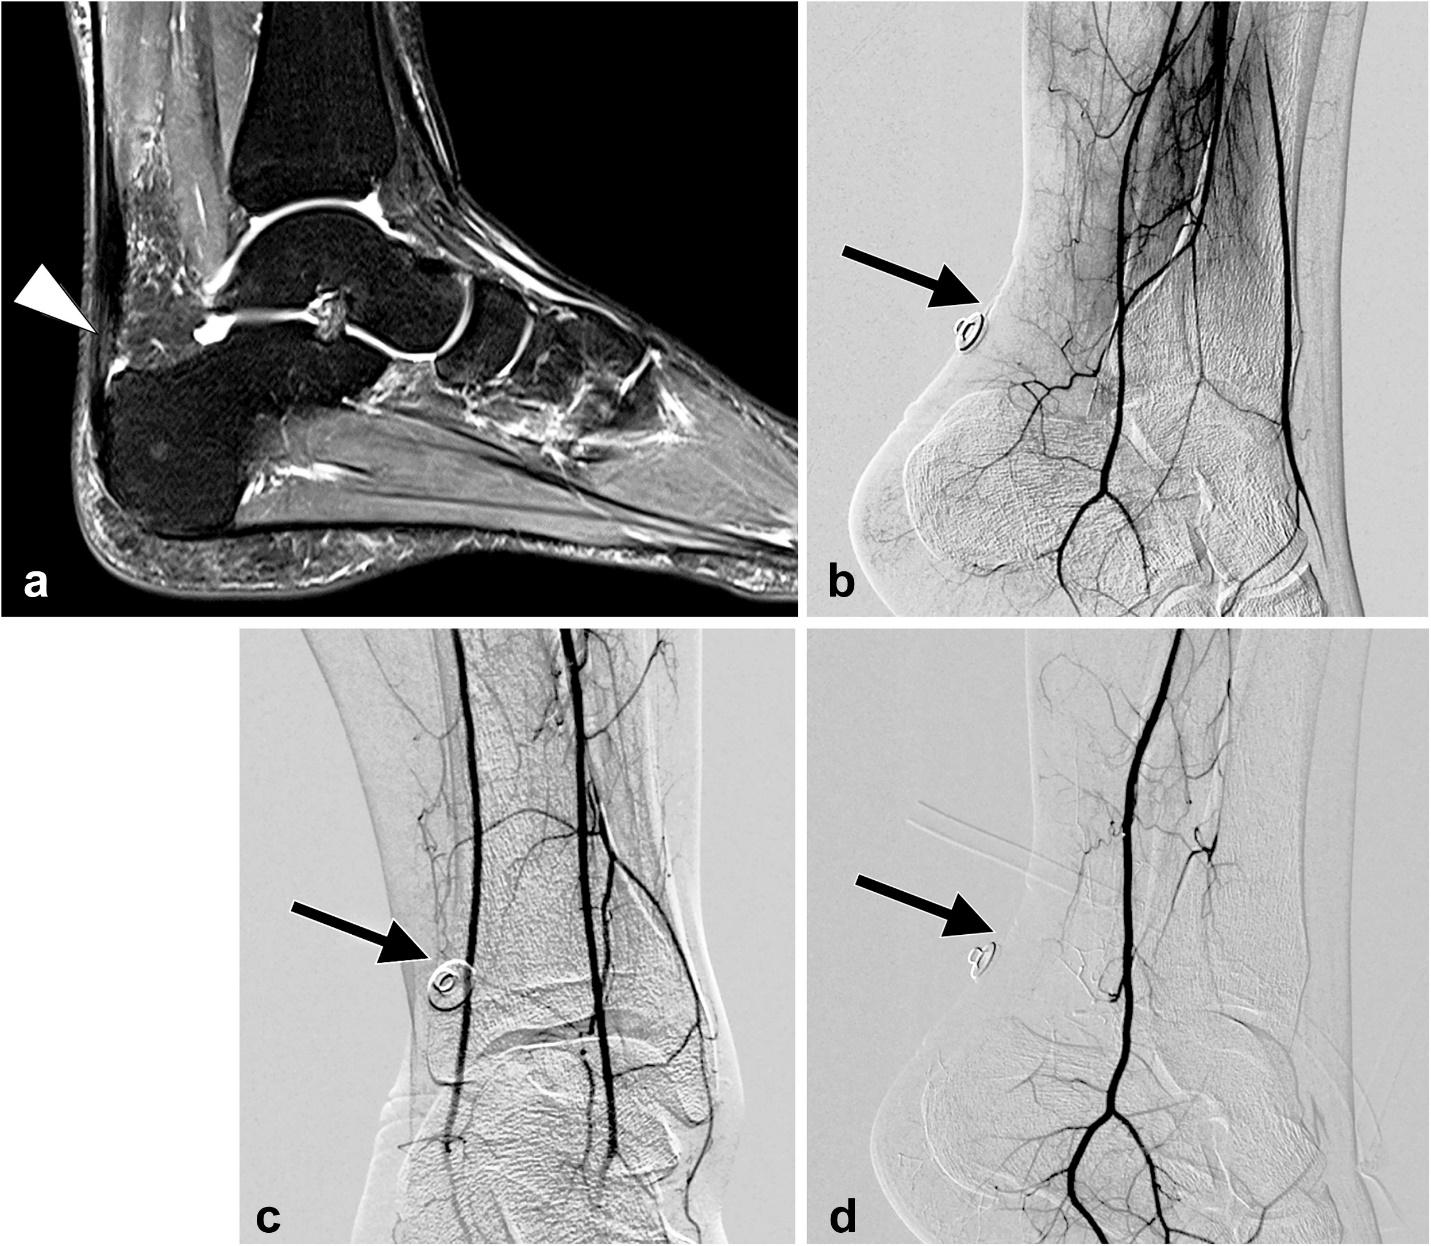

Transarterial microembolization (or Transcatheter Arterial Embolization, TAE) is a minimally invasive procedure for chronic Achilles tendinopathy that targets and blocks abnormal new blood vessels (neovascularization) that contribute to inflammation and pain. During the procedure, an interventional radiologist guides a catheter through an artery to the Achilles tendon and injects an embolic agent to cut off the blood supply to these pathological vessels, which can significantly reduce pain and inflammation. Studies suggest TAE has a good safety profile and shows promising results, with patients reporting pain reduction in 86% of cases in one pilot study, though more randomized controlled trials are needed to confirm these benefits.

A small puncture site is used for catheter insertion, resulting in a faster recovery compared to surgery.

The procedure aims to reduce inflammation and pain by targeting the vascular supply of the affected tissue.

It offers a novel, non-surgical option for patients whose tendinopathy does not respond to conservative treatments.

Studies have shown it can be effective for both insertional and non-insertional tendinopathy, including in athletes.

A pilot study of 20 patients showed an 86% success rate (at least a 50% reduction in pain score) at 6 months after embolization.

Many patients notice improvement within the first few weeks, with continued pain relief in the months following the procedure.

Studies have indicated a good safety profile with a low rate of minor side effects.